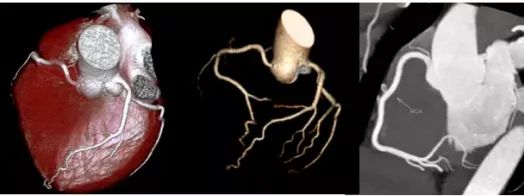

Drive双源CT的单扇区时间分辨率达到75ms,在最为复杂的心脏成像中对图像的“冻结”能力更强,真正实现了“无限制”心脏冠脉CT检查,两次吸气憋气就可以完成检查过程,图像也更加清晰。一次10秒左右的扫描即可获得整个躯干包括肺、心脏、血管及其他脏器在内的全部组织结构信息。

SOMATOM Drive CT可以实现一张胸片的辐射剂量下获得全肺的筛查CT图像,三张胸片的辐射剂量下完成冠脉CTA扫描。X线剂量较以往设备下降60%~80%,在获取高质量影像图片的同时,也保证了低剂量带来的CT检查安全。SOMATOM Drive CT行血管CTA检查(如冠状动脉、头颈部血管、全主动脉、下肢动脉CTA等检查),对比剂使用量仅为之前CTA检查的一半。